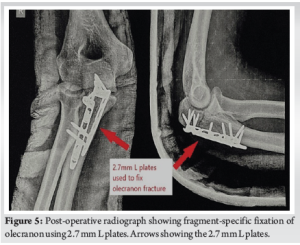

An acceptable fracture reduction was visible on a post-operative radiograph as shown in (Fig. 5). Elbow range of motion was started on post-operative day 2 as per patient tolerance.

The surgical procedure was done after routine laboratory investigations and pre-anesthesia checkup under general anesthesia with the patient in the left lateral position. After exsanguination, the upper limb tourniquet was inflated to 220 mm of Hg. A 15 cm incision was made over the posterior aspect of the right elbow via the lateral paraolecranon approach as shown in (Fig. 3). The ulnar nerve was identified and protected throughout the surgery. After elevating the triceps, the fracture site and post-erolateral and post-eromedial fragments were identified. The fracture was reduced using pointed reduction forceps and two 2.7 mm L plates were used to fix the post-eromedial and post-erolateral fragments using locking and cortical screws as shown in (Fig. 4). Final reduction was checked using fluoroscopic guidance and closure was done in layers.